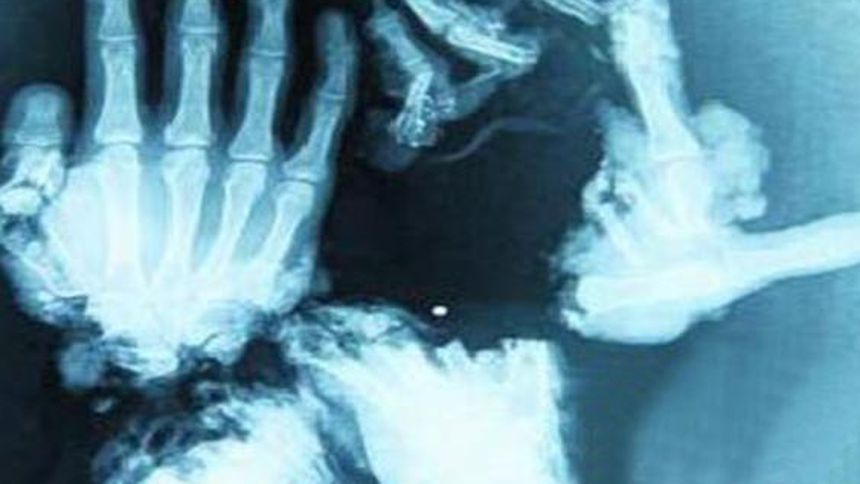

Nunca se había hecho una operación de este tipo | ESPECIAL

Los médicos decidieron que sería mejor tener dos dedos - Foto : ESPECIAL

9 horas duró la operación para formarle sus pincitas a Wang - Foto : ESPECIAL

Los médicos supieron de inmediato que esa masa de huesos molidos no podría ser reimplantada, pero los cirujanos en jefe tomar el riesgo y con los pedacitos que tenían le hicieron sus pincitas para que al menos pueda hacer trabajos sencillos.

Tardará varios meses en acostumbrarse, pero podrá mover sus dedos - Foto : ESPECIAL

La operación empezó a las 21:00 horas y terminó a las 6:00 de la mañana del día siguiente, más de nueve horas en total, y la parte más difícil fue encontrar algunos huesos que sirvieran y asegurarse de que la circulación de la sangre se lograra. La operación fue un éxito y ahora Wang puede mover sus dedos.